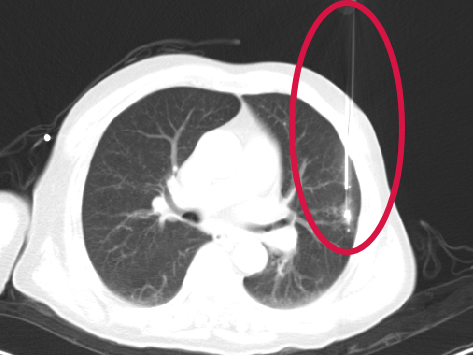

第一根消融針置入

▲患者因體檢發(fā)現(xiàn)左肺上葉舌段結(jié)節(jié),考慮周圍型肺癌可能。因高齡、肺氣腫無法手術(shù),遂來院接受肺結(jié)節(jié)冷凍消融治療,術(shù)后病理為肺癌,定期隨訪提示腫瘤逐漸縮小。